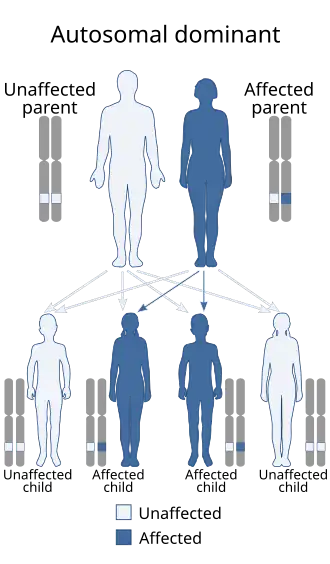

DiGeorge syndrome is typically due to the deletion of 30 to 40 genes in the middle of chromosome 22 at a location known as 22q11.2.[3] About 90% of cases occur due to a new mutation during early development, while 10% are inherited.[7] It is autosomal dominant, meaning that only one affected chromosome is needed for the condition to occur.[7] Diagnosis is suspected based on the symptoms and confirmed by genetic testing.[5]